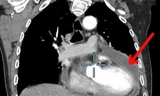

| Hình ảnh kiểm tra phát hiện vị trí dị dạng mạch máu tủy ở bệnh nhân |

N. được người quen giới thiệu đến bệnh viện S.I.S Cần Thơ và được chỉ định chụp cộng hưởng từ (MRI). Từ kết quả hình ảnh học, các bác sĩ phát hiện khối dị dạng mạch máu lớn chèn ép vùng tủy sống, gây phù tủy và tổn thương hệ thần kinh nghiêm trọng.

TS.BS Trần Chí Cường, Giám đốc Bệnh viện Đa khoa S.I.S Cần Thơ cho biết: "Thông thường, đường kính tủy sống khoảng 2cm. Tuy nhiên, ở bệnh nhân này, túi phình dị dạng lên tới gần 2,4 cm, chèn ép hoàn toàn vùng chóp cùng tủy – nơi có chùm đuôi ngựa chi phối vận động hai chân. Đây là nguyên nhân khiến bệnh nhân đau dai dẳng và yếu cơ tiến triển”.